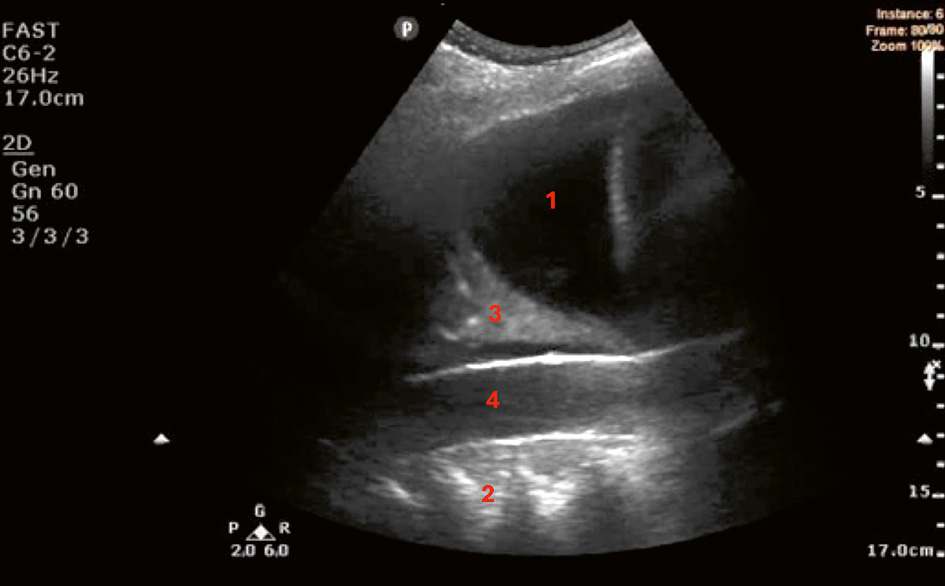

Sonografiskt utseende av pleuravätska (A–D). Pleuravätska identifieras med ultraljud som ett spatium mellan pleura parietale och pleura viscerale [48] och kategoriseras enligt ekogenitet och innehåll [49].

B. Komplex icke-septerad pleuravätska (svart vätska med icke-homogena vita ekon motsvarande fibrin, protein, blod eller var) hos en 19-årig man med icke-infekterad para­pneumonisk pleuravätska. I bilden syns punktformiga fritt flytande ekon (»plankton sign«) [50].

C. Komplex septerad pleuravätska hos en 83-årig man med primär pleurainfektion.

D. Komplex homogen pleuravätska (gråaktig uniform ekogenitet) hos en 37-årig man med empyem. Anekoisk och komplex icke-septerad pleuravätska kan vara exsudat eller transsudat [51-53]. Septerad och komplex homogen pleuravätska har däremot 96 procent positivt prediktivt värde för exsudat [53]. Komplex homogen pleuravätska är oftast empyem eller blod [48].